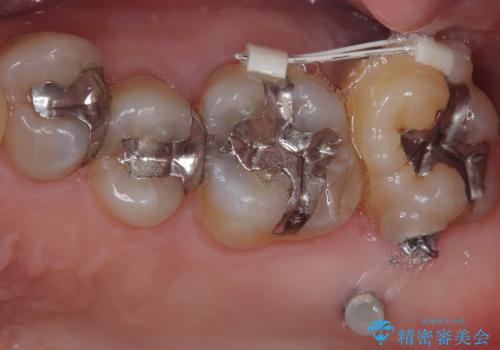

- 奥歯のむし歯治療を希望して来院された患者様です。

上顎の奥歯は、左右ともに外側に転位しており、特に右上はむし歯の範囲が広く、根管治療も必要な状態でした。

上顎左右の歯をアンカースクリューを用いた部分矯正により位置を修正し、オールセラミッククラウンにて補綴治療を行うこととしました。